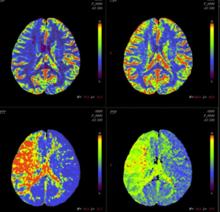

醫學圖像分析的目的是得到生理過程的定量信息,為臨床診療提供更充分的依據。過去的醫學成像主要集中在解剖結構成像和形態分析上。近年來,醫學設備成像速度的飛躍使對生理過程的動態觀察成為可能。例如:在腦功能成像領域,Functional MRI開始廣泛套用;核醫學PET(positron emission tomography)和SPECT(single photon emission computer tomography),在腦功能和心功能動態成像方面也得到廣泛的套用;MR心功能成像方面,標記MR技術(Tagging)和相位對比MR成像技術,在物理上為圖像定量分析心功能提供了依據;另外,三維超聲的出現,提供了實時觀察心室和瓣膜運動的手段。以上設備都能生成產生時序的二維或三維醫學圖像,反映了生理過程的動態功能信息。相應的醫學圖像分析也由圖像處理範疇的圖像分割、配準技術,向以醫學圖像為媒介,精確、定量地分析器官的功能和生理過程發展。

醫學圖像分析圖4. 腦部灌注分析